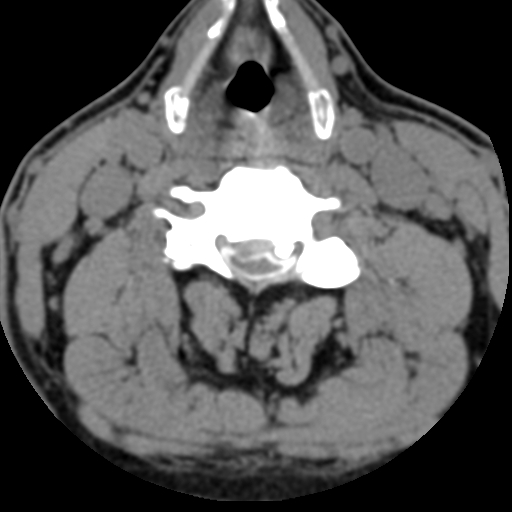

术后CT见减压充分,螺钉位置良好